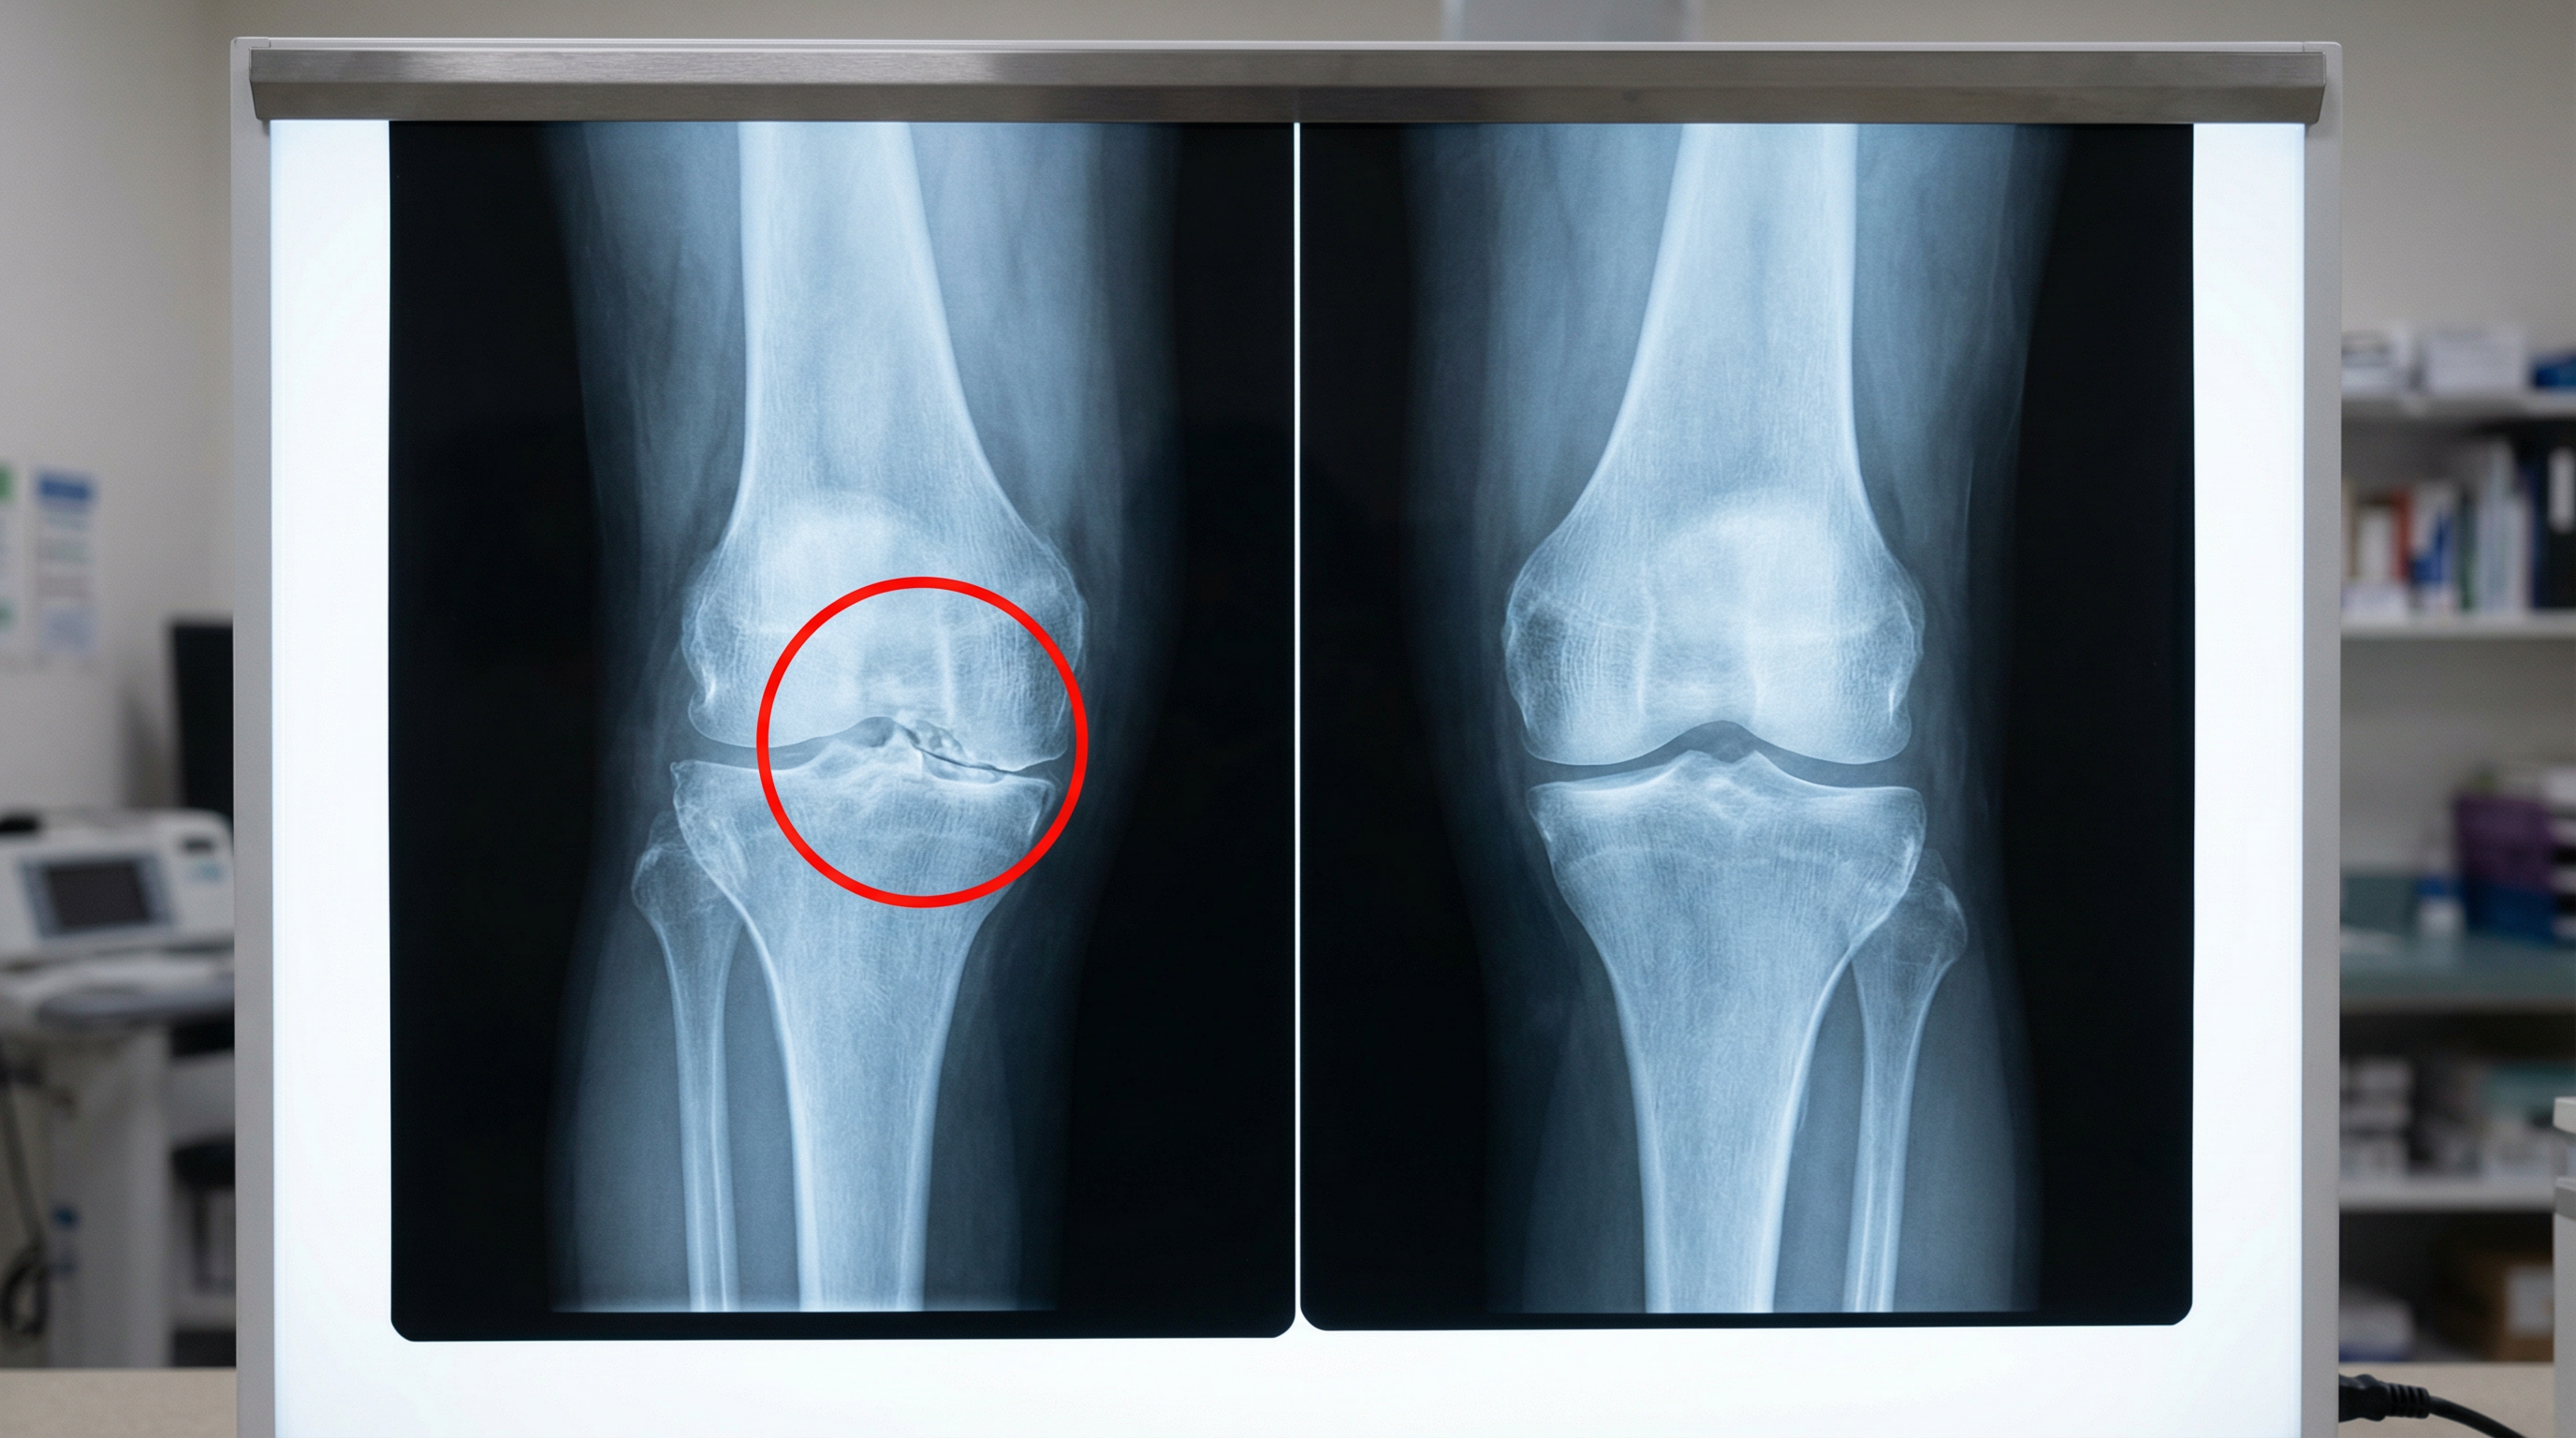

When this deterioration occurs, you develop bone-on-bone contact. The single most agonizing condition any knee can experience.

THE TRUE CAUSE OF BONE-ON-BONE KNEE PAIN

Imagine your knee cartilage functioning like a kitchen sponge.

In your younger years, that sponge remains thick, supple, and saturated with fluid.

It provides cushioning for your joints and maintains proper bone separation, keeping your knees functioning smoothly.

But here's the devastating reality after crossing the 40-year threshold...

That protective sponge begins hemorrhaging fluid. Becomes progressively thinner.

Desiccates completely. Like leaving a sponge abandoned in desert heat.

Your bones migrate closer together.

The cartilage grows increasingly compromised.

And your knee?

Gets compressed like that sponge crushed beneath heavy machinery.

The medical establishment has known about this for decades.

This information has been documented since 1987, when Scandinavian researchers conclusively demonstrated that 91% of chronic knee pain sufferers exhibited "severe cartilage dehydration."